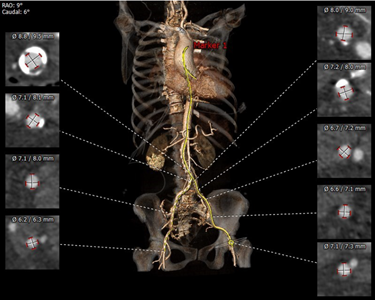

血管入路解剖

双侧股动脉直径均较小,髂总分叉上可见团块状钙化,双侧股动脉均可见钙化点,分叉均较高。但股浅动脉直径可作为主入路。

经过团队严谨的评估及充分的讨论,决定先行18mm球囊预扩并进行瓣环测量(备20mm球囊),并优先准备AV23的瓣膜装载(备AV26瓣膜);由于股动脉入路情况不佳,决定选用TaurusElite™经导管主动脉瓣系统DS19S型号的输送器,输送器自带内联鞘,可进行瓣膜的无鞘输送。

术后,陶主任对TaurusElite™可回收输送器过弓性能和瓣膜释放稳定性给予了高度评价,对输送系统可通过6.2mm直径的股动脉也给予了肯定。